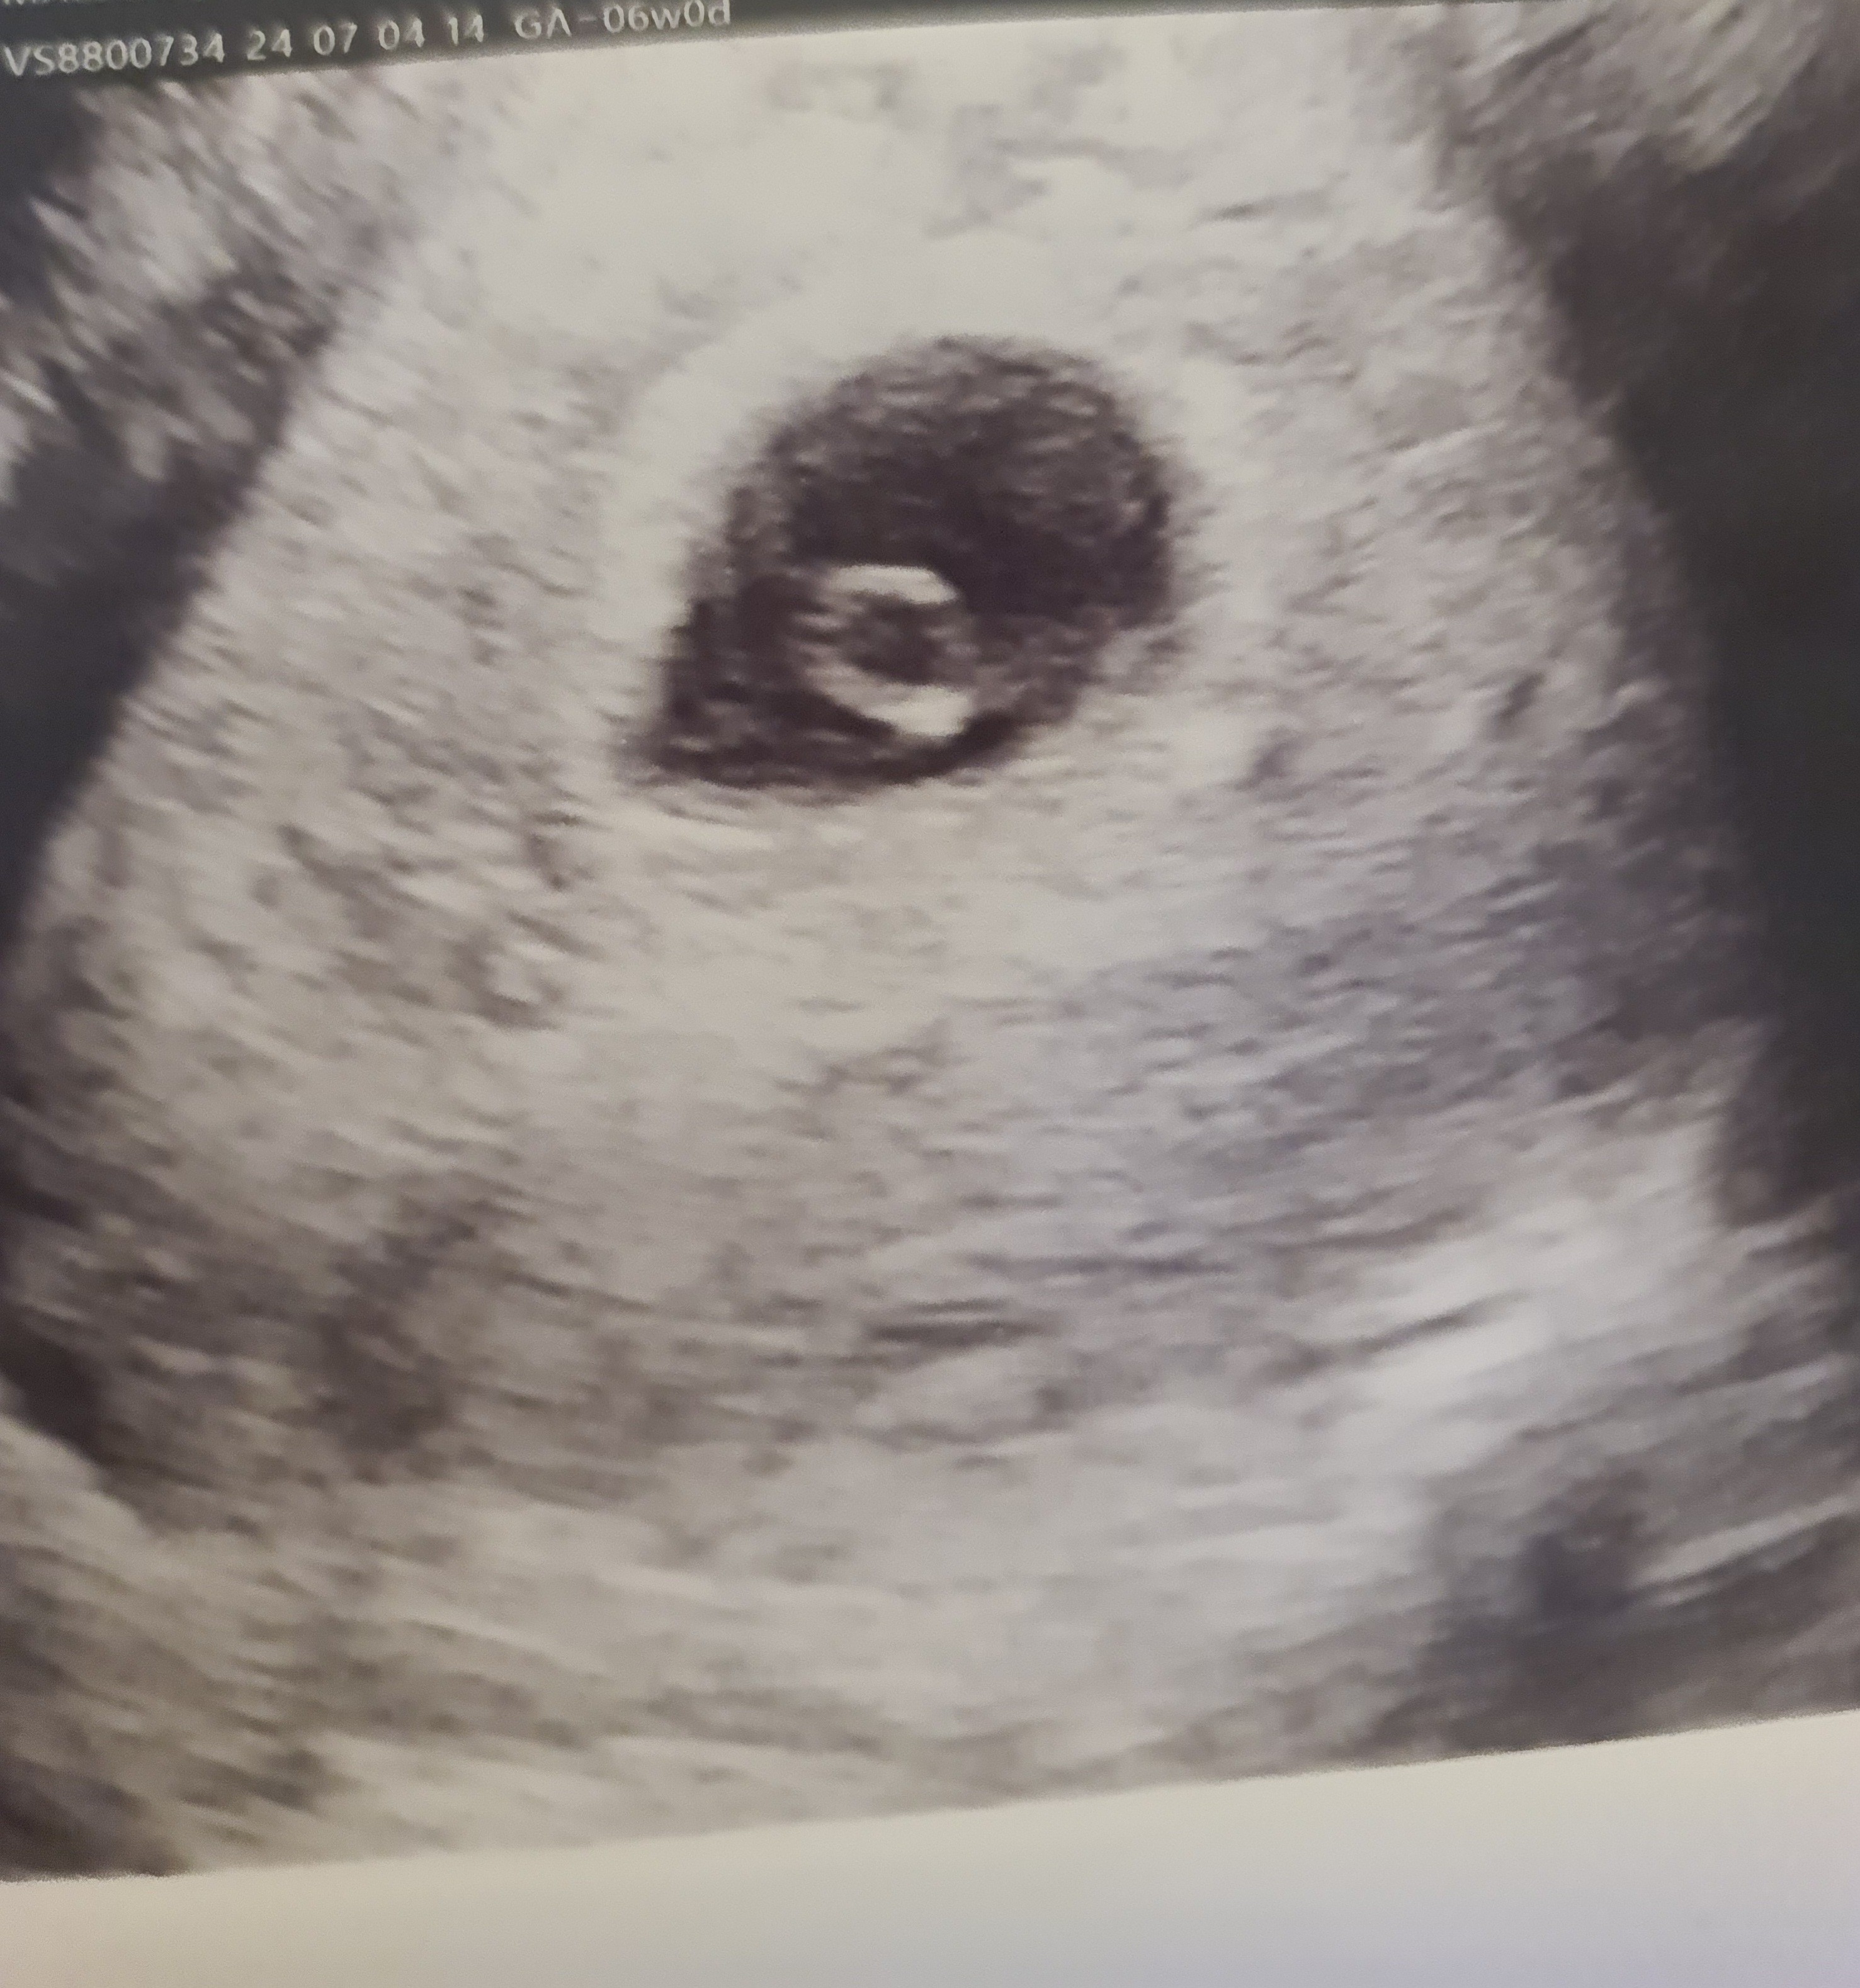

Pokażesz swoje zdjęcie usg które dostałaś?(jeśli chcesz oczywiście) Co na nim widać?